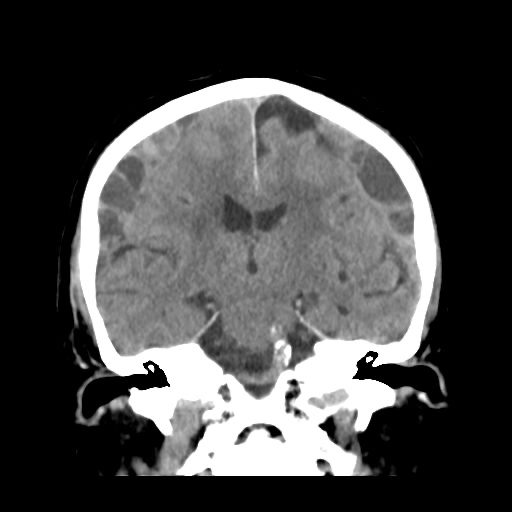

CT

当院が導入しているシーメンス社製の64列CT「SOMATOM go.Top」は、※逐次近似法の技術を搭載しており、短時間で精細な画像を提供します。この装置は、特に頭部の撮影においてその真価を発揮します。脳神経外科専門病院である当院において、頭部外傷、脳出血、くも膜下出血、骨折などの緊急を要する疾患の診断には不可欠な存在です。迅速な撮影により、病態を正確に把握し、一刻を争う治療へと繋げています。

撮影件数:2023年 5823件/2024年 5984件